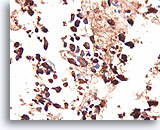

Afbeelding 13

Benigne, hyperplastisch/adenomatoïde nodule, schildklier FNA, celblok.

Het celblok dat overeenkomt met afbeelding 11-12 toont een duidelijk bijvoeging van micro- en macrofollikels. Er zijn twee kenmerken die voor een benigne nodule pleiten. Het eerste is dat de microfollikels afgeplat cytoplasma vertonen, vergeleken met de robuuster uitziende macrofolliculaire cellen (vergelijk de hoogte van het cytoplasma bij de twee pijlen). Een tweede kenmerk is de variatie in het uiterlijk van het colloïd tussen de verschillende follikels. Let op het oedemateuze colloïd in het ene follikel dat zich naast een follikel bevindt met dicht opeengepakt colloïd (open pijlen). Van benigne hyperplastisch/adenomatoïde nodulen wordt verwacht dat ze heterogeniteit vertonen, terwijl folliculaire neoplasmen monotoner zijn.

40X